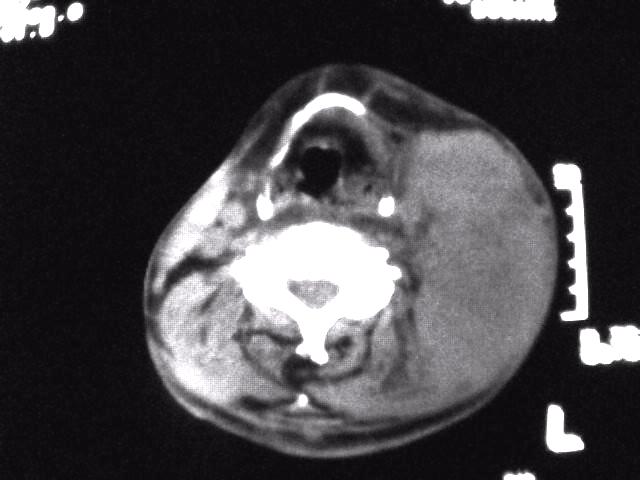

颈部层厚10mm间距10mm连续扫描及增强扫描共24层示:左侧下颈部胸锁乳突肌内侧区域内可见多发软组织结节,密度不均,内可见斑片状低密度区,大小不等,部分融合成块,左侧融合成一块者大约9.0x5.4,与周围肌肉、血管等结构界面不清,骨质未见明显浸润影。左侧锁骨下可见多个软组织结节,与周围界限尚清,左侧锁骨上窝内可见一大软组织肿物,大小约4.7x3.7cm,内密度欠均匀中心可见低密度区。

考虑:左侧颈部及双侧锁骨下多发淋巴结肿。非何杰金氏淋巴瘤可能性大,建议进一步检查。